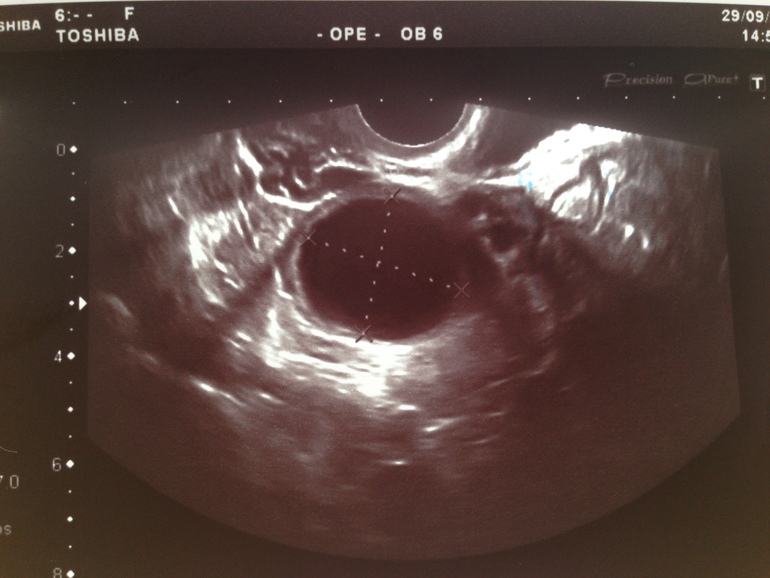

Вот например подтвержденное ЖТ и тоже около 30 мм.

Ну и где тут что неровное? И где вкрапления?А вот вам киста (под вопросом):

Отличить сложно. Но если есть жидкость,а у вас есть, тогда это ЖТ.